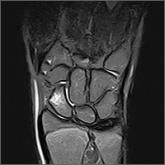

ArticleBilateral wrist pain • limited range of motion • tenderness to palpation • Dx?Author:Hannah Shehata, MD, MBAPublish date: March 1, 2018► Bilateral wrist pain► Limited range of motion► Tenderness to palpationRead More